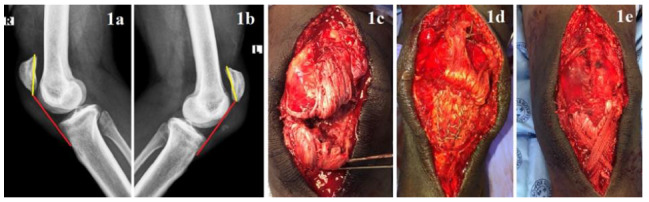

Bilateral patellar tendon ruptures are exceedingly uncommon, especially when they occur in individuals without predisposing risk factors or systemic disease. Due to its rarity, many cases are missed on initial presentation resulting in poor patient outcomes. Identifying associated risk factors aids in diagnosis and mitigates this oversight. We report a case of a healthy, recreational weightlifter who sustained bilateral patellar tendon ruptures during an acute high-loading resistance exercise bout. We discuss how a spike in acute workload may have predisposed our patient to this injury. Research into training load and athlete injury risk is currently in vogue, however, no studies have analysed whether poor load management increases the risk of tendon ruptures. This case prompts awareness for clinicians who diagnose and manage this injury and helps to stimulate the formation of educational initiatives for athletes and coaches, aimed at injury prevention.